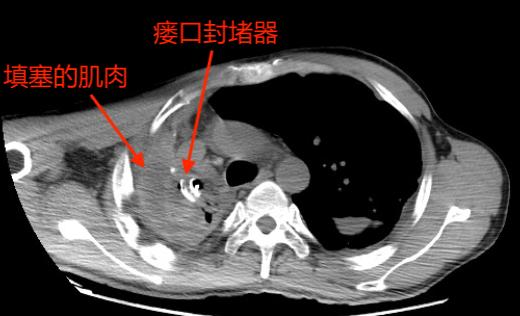

入院后,胸部CT检查提示“右上胸腔见团状包裹积气积液,局部与支气管相通,引流管留置。”随后呼吸科胡蕙蕙副主任医师又给杜先生进行了支气管镜检查,发现“右上叶尖段可见瘘口,透过瘘口甚至可见胸腔的两条引流管。”

最终,专家们决定进行多学科联合手术。由呼吸科先进行支气管镜下瘘口封堵;然后,胸外科胸腔镜下清创;最后,由沈立锋副主任医师进行肌肉瓣覆盖瘘口、完全填塞胸腔彻底消灭脓腔。

手术按部就班地进行着,顺利地进行支气管瘘口封堵,然后是胸腔镜清创,就差沈医师的肌肉瓣手术了。

起初,沈医师决定用体积大、血运又非常丰富的背阔肌来填塞胸腔。

然而,手术总是存在各种变化。沈医师发现,多年的肺部疾病使杜先生丧失了大部分劳动能力,肌肉严重萎缩,单独用这块肌肉填塞胸腔,远远不够。

医生的智慧显得尤为关键,经验丰富的他当机立断,马上调整手术方案,选择增加背阔肌和胸大肌两组肌瓣联合填塞关闭胸腔。

镜支气管镜检查确定瘘口后,选择合适大小的金属封堵器置入封闭瘘口。但是单纯做封堵的失败率高,瘘口周围血运较差,没有软组织覆盖,内植物与周围组织愈合不良,加之脓腔未消灭,脓液刺激,导致瘘口扩大,封堵器松动失败。

运用肌瓣、大网膜等自体组织对脓腔进行填塞,可彻底治愈脓胸。临床上最常用的为背阔肌、胸大肌、腹直肌瓣或肌皮瓣。肌皮瓣不仅有足够的体积和面积填补胸腔、修补皮肤溃疡,并且其丰富的血供可以有效地进行局部抗炎。带有丰富血运的肌肉组织覆盖内置封堵器并与周围组织愈合,亦可以辅助关闭瘘口,防止再发。所以肌皮瓣是消灭脓腔的最佳选择。肌皮瓣的选择要根据脓腔的大小、形状以及位置而定,常可多块联合应用治疗。